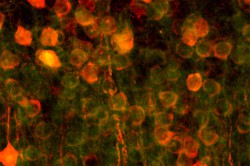

Auch die Strömung der Luft durch die Lungen sowie der Druck und der reine Stress durch das Blut und extrazelluläre Flüssigkeit üben mechanische Kräfte auf die Zellen aus, wie Muiznieks erklärt. Durch die Nachahmung dieser Strömungen auf einem Mikrofluidik-Chip werden die Forschenden außerdem in der Lage sein, auf effizientere Weise Zellnährstoffe zu verabreichen und Zellabfall zu entfernen. „Das Lung-on-a-Chip-Modell soll nicht das gesamte Organ ersetzen, sondern dient dazu, eine kleine Untergruppe von spezifischen Funktionen nachzuahmen – in diesem Fall die Luft-Flüssigkeit-Grenzfläche der Alveolaroberfläche“, merkt Muiznieks an. Um eine möglichst realistische Oberfläche zu erreichen, wurden die Zellen an eine dünne Proteinmatrix gebunden. „Alle Zellen sitzen auf einer extrazellulären Matrix, also einem Netzwerk aus Faserproteinen wie Kollagen, Fibronektin und Elastin“, fügt Muiznieks hinzu. „Durch eine künstliche Membran aus den gleichen Proteinen können wir diese Umgebung für Zellen nachahmen.“ Genau diesem Ziel solcher künstlicher Membranen galt ihre bisherige Forschungslaufbahn. Mit Unterstützung im Rahmen der Marie-Skłodowska-Curie-Maßnahmen(öffnet in neuem Fenster) zog Muiznieks nach Frankreich, um dort gemeinsam mit dem Projektträger Elvesys(öffnet in neuem Fenster), einem Mikrofluidik-Unternehmen, an der Entwicklung von Lung-on-a-Chip-Modellen zu arbeiten. Nach Abschluss ihres Stipendiums im Oktober 2020 wurde sie als Vollzeit-Mitarbeiterin bei Elvesys übernommen. „Wir haben bereits Prototypen, allerdings besitzen diese noch keinen ausreichenden technologischen Reifegrad. Bis dahin ist noch weitere Forschungsarbeit nötig“, erklärt Muiznieks. „Wir haben das Gerüst entwickelt, die Membran hergestellt, in den Mikrofluidik-Chip eingebettet und zur Validierung getestet, indem wir Zellen zugefügt haben und anwachsen ließen, und konnten den Kanal perfundieren.“